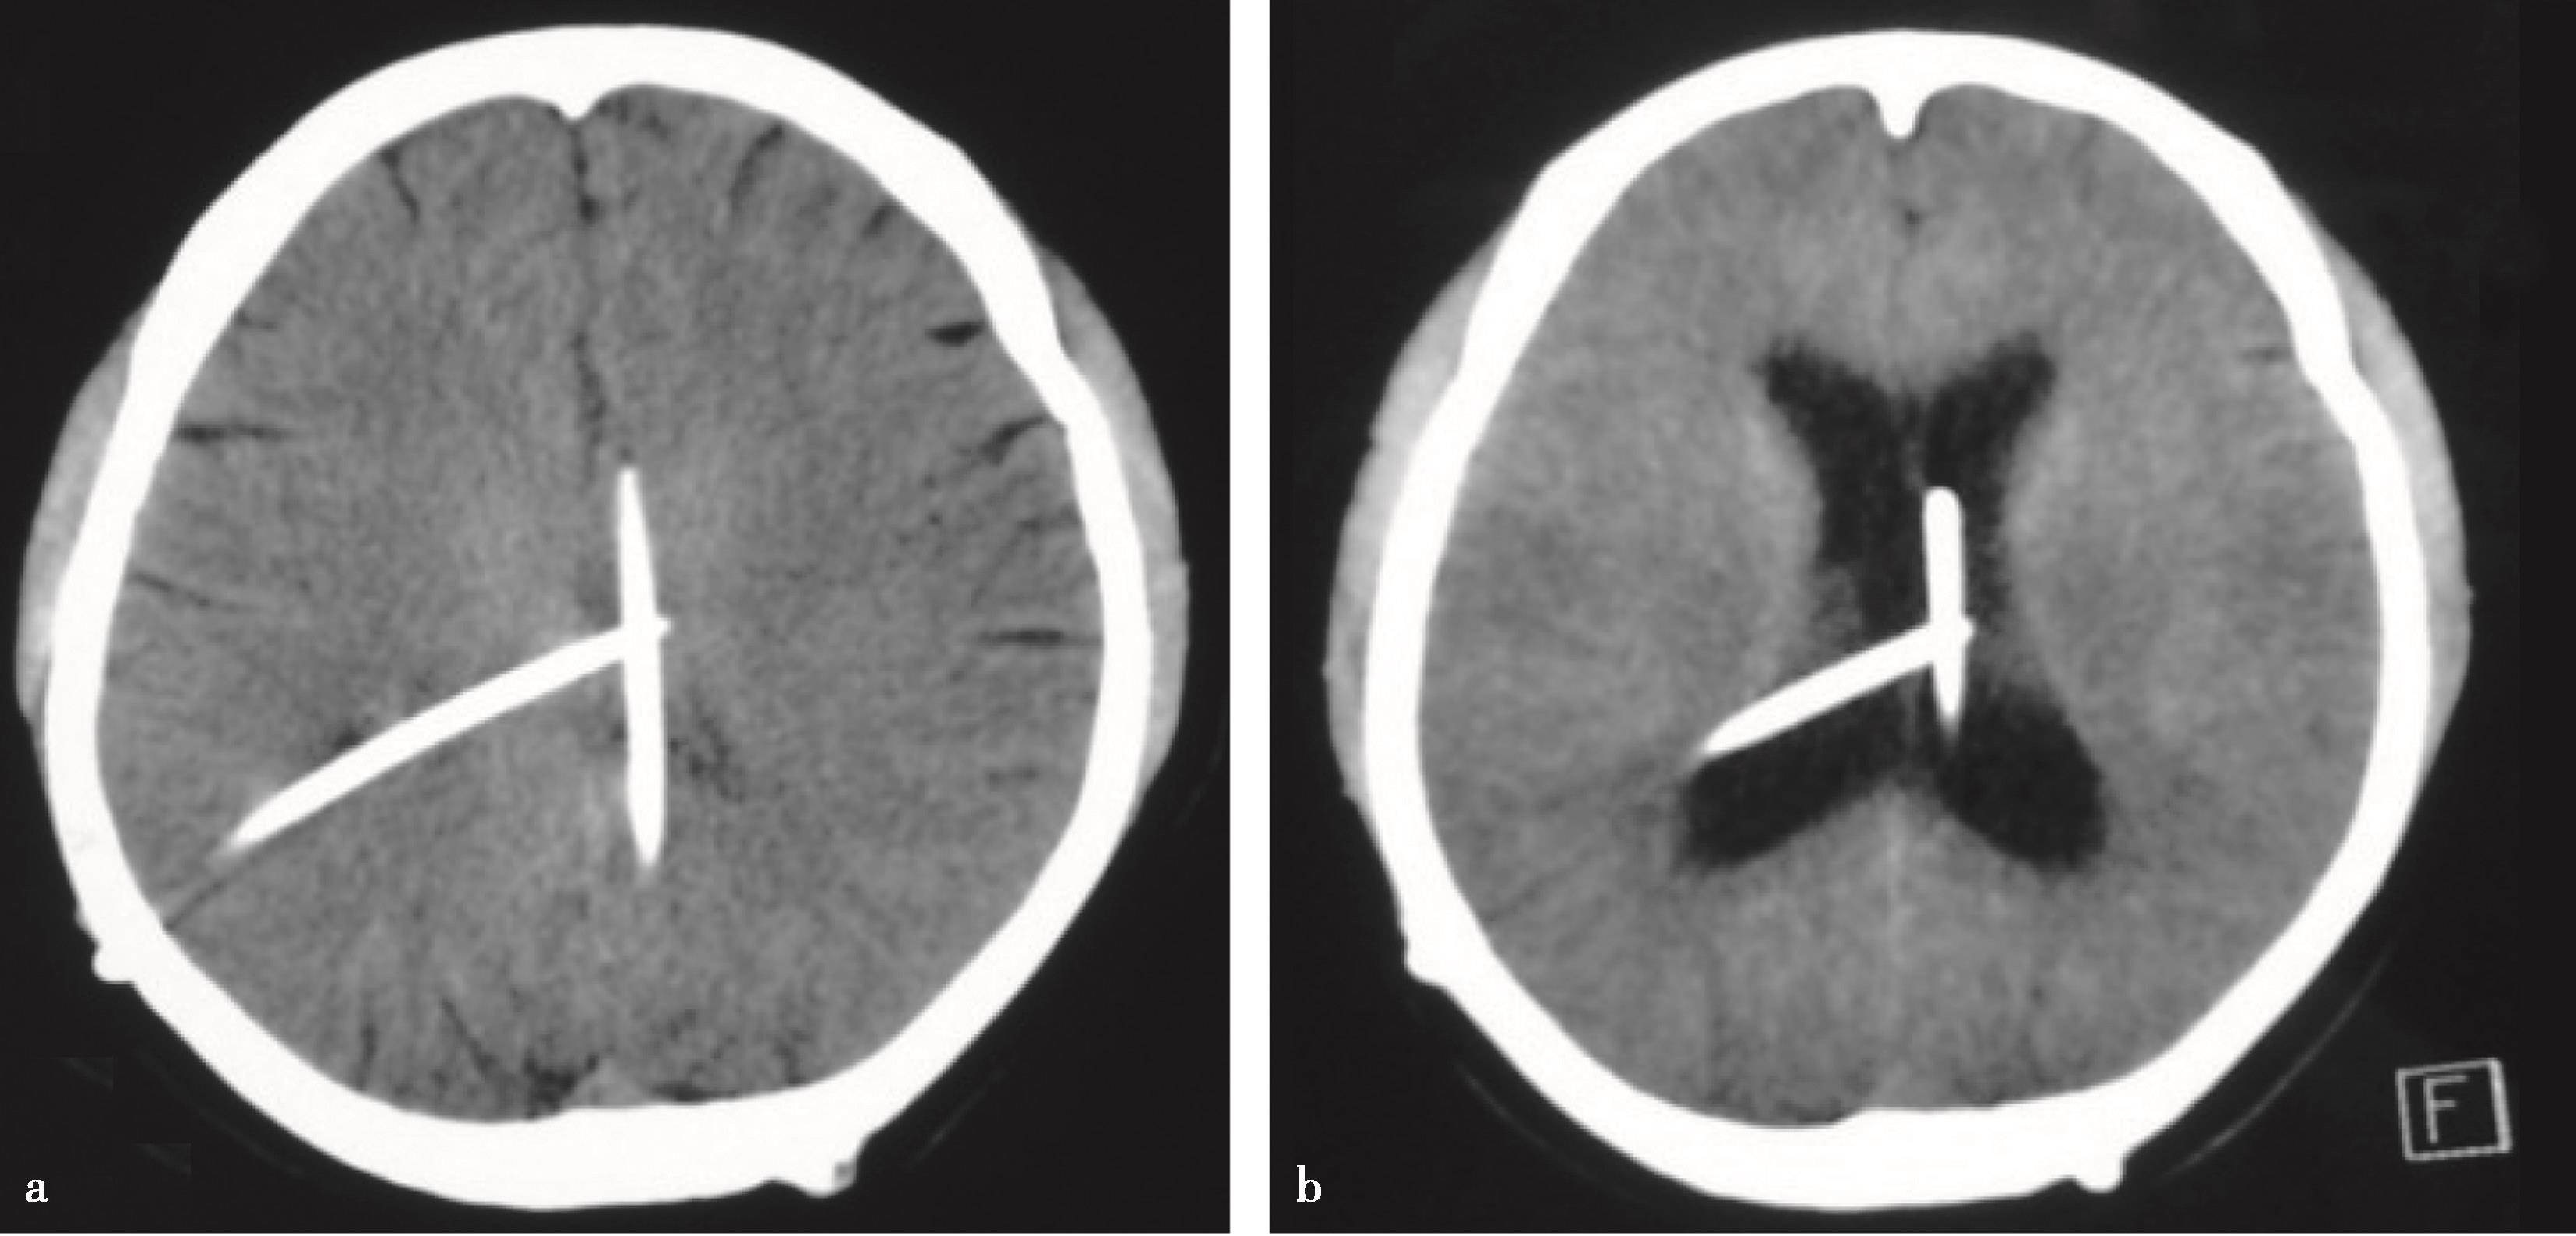

图3-1-1-1 出血后脑积水的脑室演变

a.发病时头颅CT:脑室内血肿呈高密度;b.发病12天后复查CT:血肿已呈低密度;c.发病5个月后头颅MRI:脑室明显扩张,脑室内未见异常信号;d.内镜下探查见脑室内仍有陈旧血斑及含铁血黄素沉积